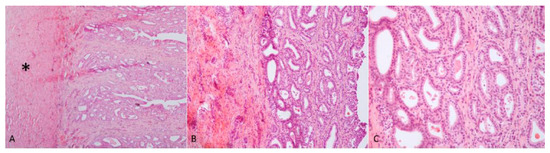

Case 1: The testes were grossly enlarged up to two or three times their normal size (25 × 20 cm). In the cut surface, there was a massive abscess and severe, diffuse, dry, grey-yellow necrosis resulting in the complete destruction of testicular parenchyma (Figure 1C). The epididymis was characterized by foci of diffuse thickening and fibrinous adhesions of the testicular vaginal tunics. Fibrotic tissue was also adherent to the tunic and scrotum. A tubular structure of small diameter with a cul-de-sac end and attached to the testis was observed. This structure was soft at sectioning, and the internal wall showed a diffusely pink surface and no fluid in the lumen (Figure 1D). Histological examination of the testis and epididymis revealed a diffuse area of caseo-necrosis, effacing 98% of the normal architecture and compressing, separating, surrounding and replacing the seminiferous tubules (Figure 5A). Necrotic debris was admixed with degenerate neutrophils, encircled by foamy macrophages (Figure 5B) and occasionally surrounded by granulation tissue and abundant collagen (fibrosis). In the remaining seminiferous tubules, there was diffuse germ cell atrophy with lack of spermatids. Epidydimal epithelia were surrounded by a mild, chronic, inflammatory infiltrate consisting mostly of lymphocytes and associated with severe fibrosis (Figure 5C). Microscopic examination of the tubular structure was interpreted as a uterine tube characterized by an outer layer of connective and hypo-trophic muscle tissue with few vessels and an inner layer compatible with endometrium (Figure 6A). The endometrial tissue was characterized by a stratified epithelium with numerous simple and slightly hyperplastic tubular uterine glands (Figure 6B,C). No ovarian tissue was macroscopically and microscopically visible.

Figure 6. (A) Endometrial tissue characterized by an outer layer consisting of connective and hypo-trophic muscle tissue (asterisk) and an inner layer consisting of stratified pavement epithelium; (B,C) the epithelium was characterized by numerous, simple and slightly hyperplastic tubular uterine glands. Haematoxylin and eosin staining.